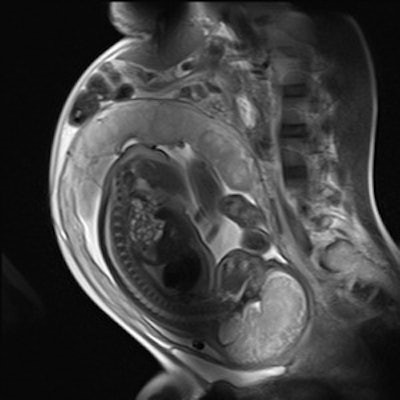

| Sagittal HASTE image used for planning further fetal images in other planes, taken at the Clinical Research Imaging Center, University of Edinburgh. Image courtesy of Janet De Wilde, PhD, and Dr. Scott Semple. |